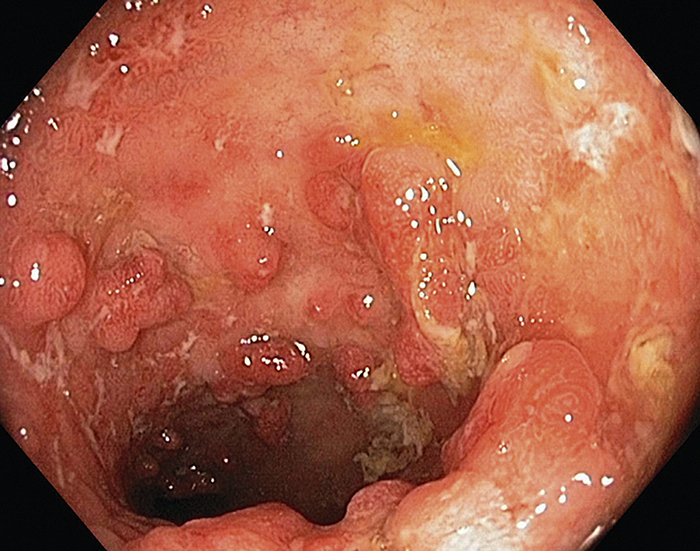

Hämmare av tumörnekrosfaktor alfa används bl a vid behandling av inflammatorisk tarmsjukdom, som t ex Mb Crohn (bilden).Foto: Gastrolab/SPL/IBL